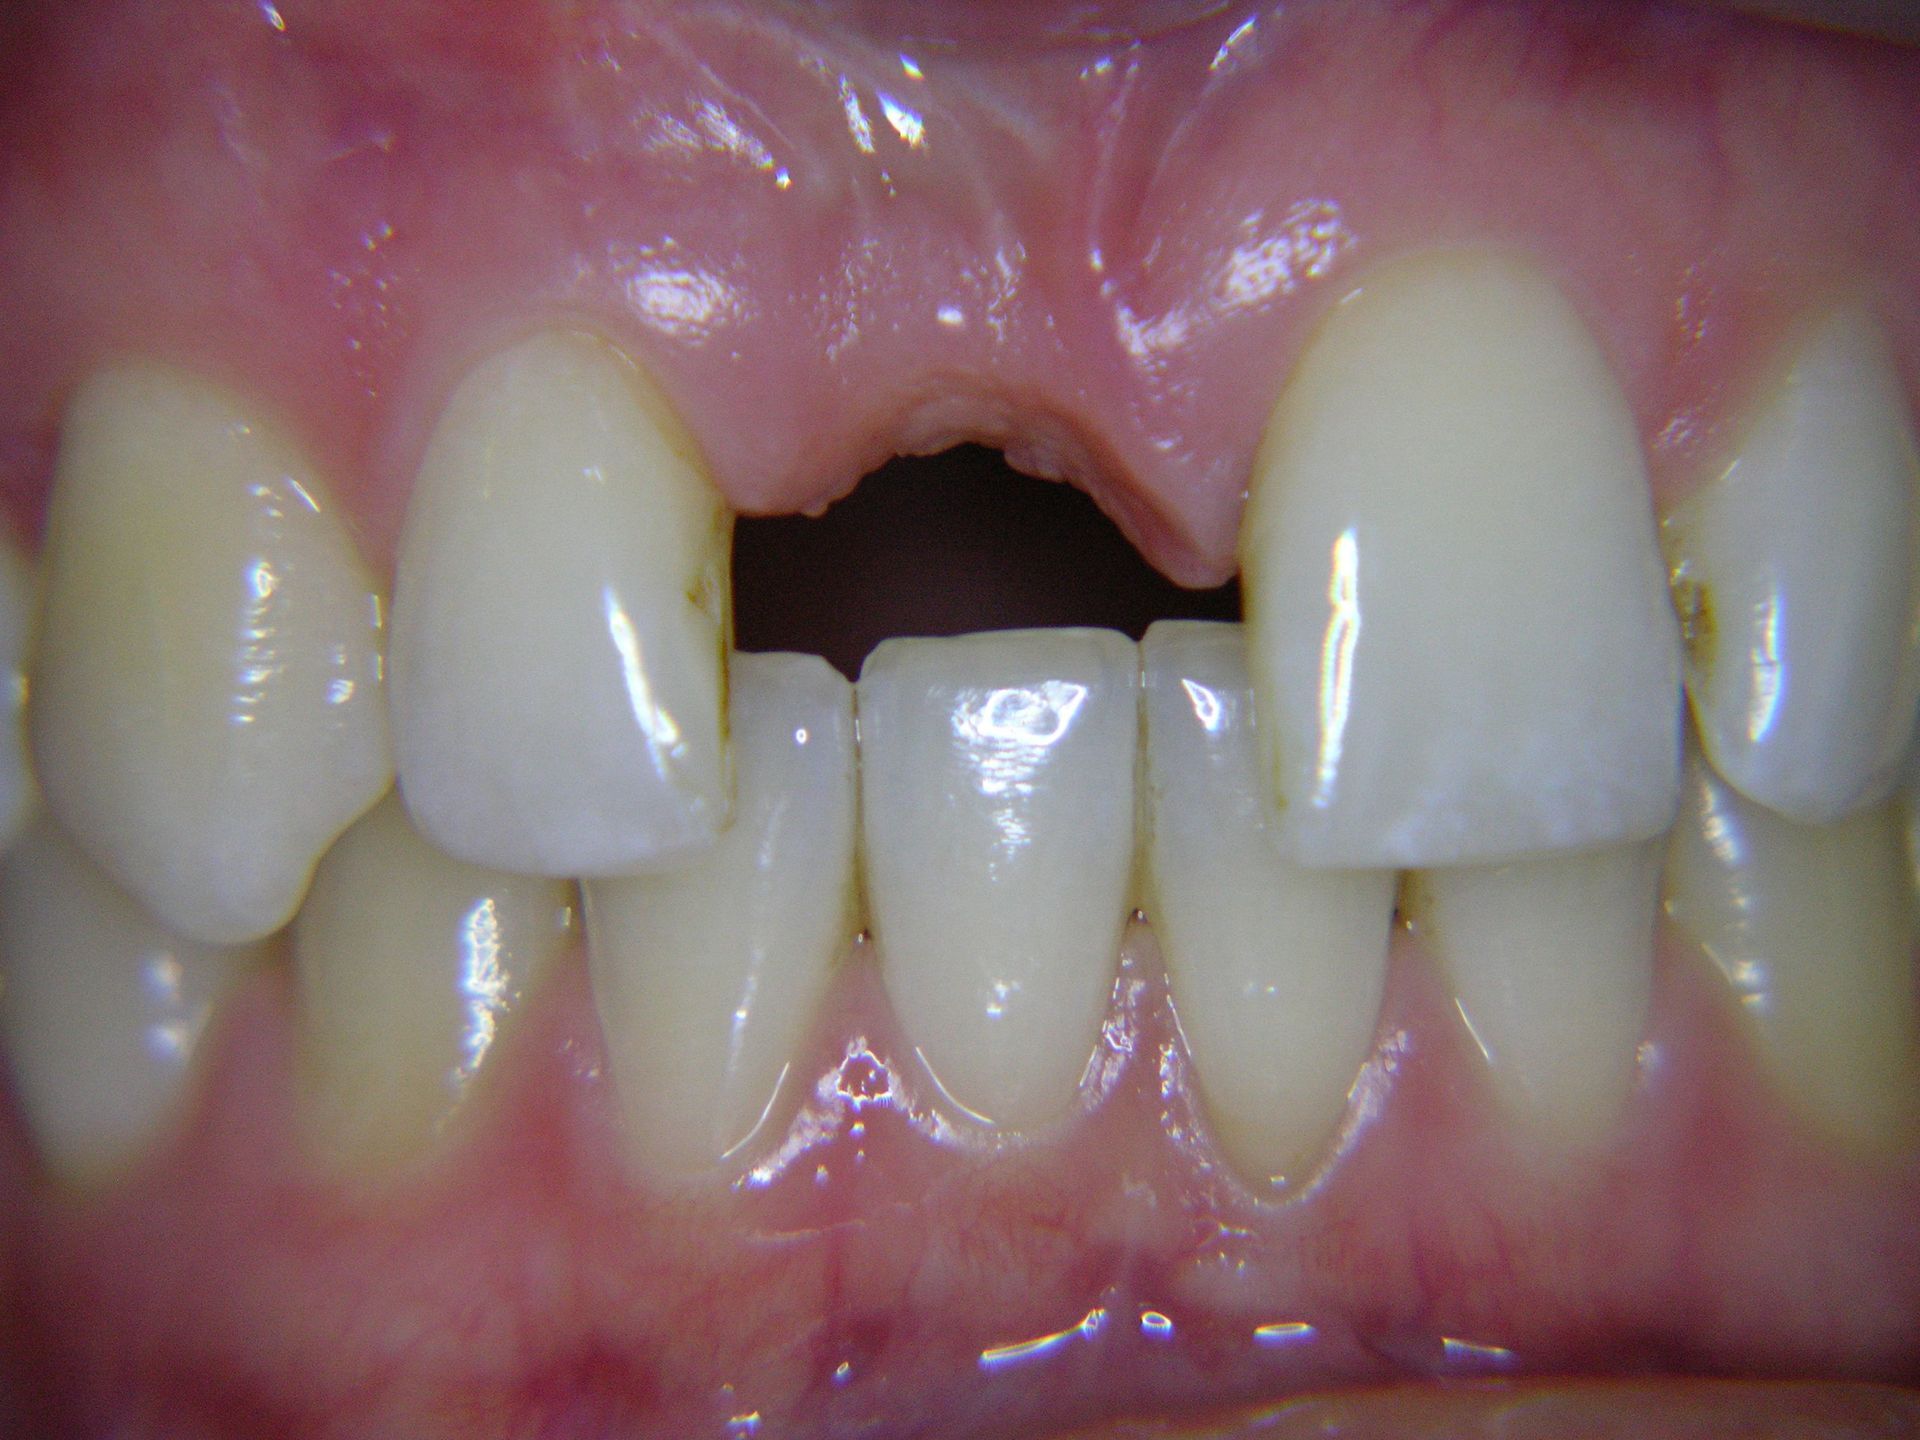

Beispiele von Versorgungen